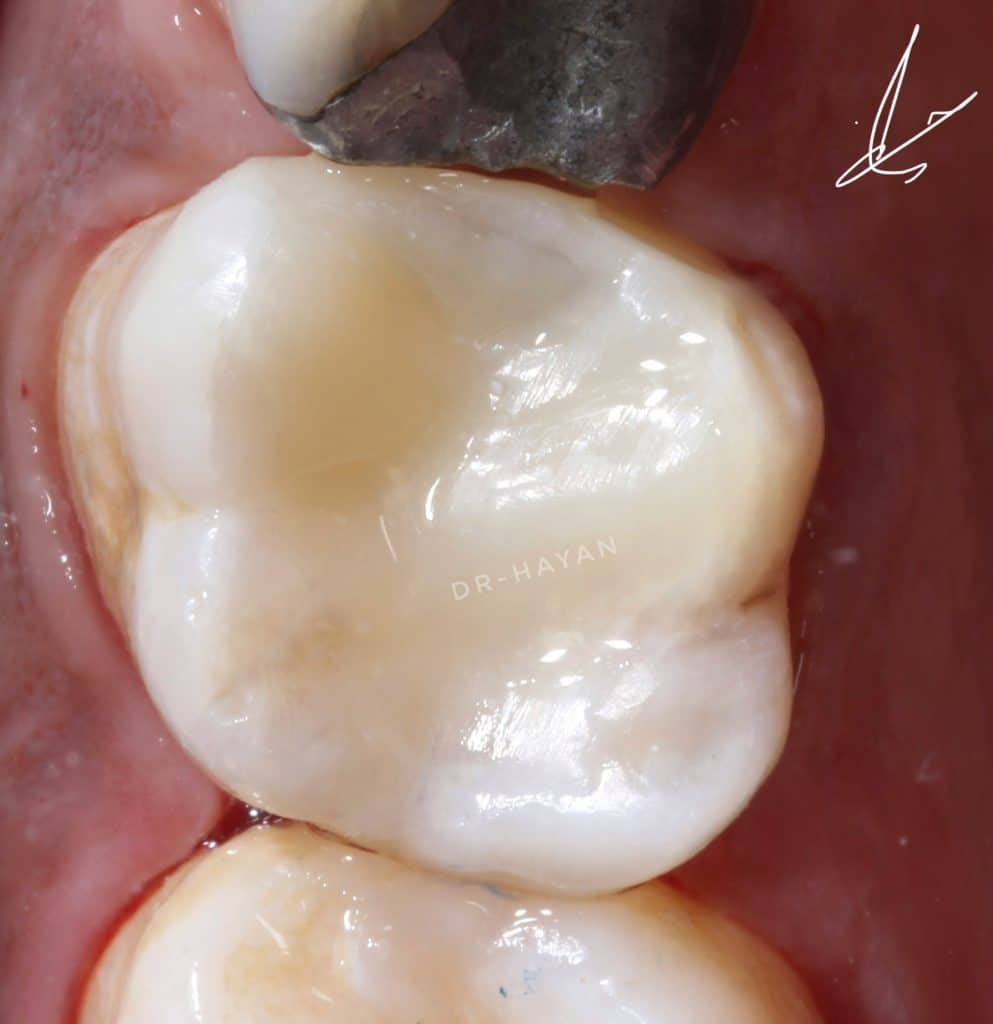

After finishing and polishing

Lateral view

After rubber dam removal and extra polishing